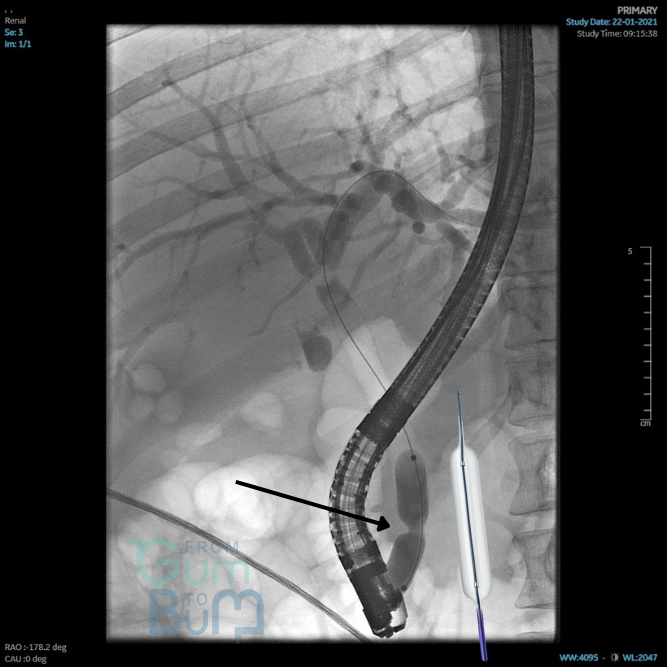

77 yo female comes with severe lower GI bleeding with haemodynamic instability that keeps bleeding and responding only partially to IV Fluids, persisting mildly hypotensive and tachicardic.

She has had a couple of similar episodes in the last year, all were suspected to be due to diverticular haemorrhage in the setting of taking Apixaban for AF but never studied.   A new CT angio suggests blood content in proximal left colon with multiple pancolonic diverticular orifices but no clear bleeding point and no other abnormalities. She is still passing some blood quantity but this has reduced.

Which next step  would NOT be recommended